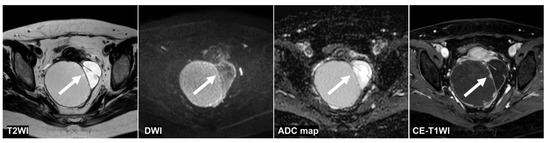

Figure 4.

A 51 year old woman with a seromucinous borderline tumor. Only the CNN could diagnose malignant tumors on the T2WI and the DWI (the CNN confidence value: malignant = 98.5% on T2WI; malignant = 99.9% on DWI). The CNN and reader 2 could diagnose malignant tumors on the ADC map (the CNN confidence value: malignant = 82.1%). On the other hand, the CNN and all radiologists could diagnose malignant tumors on the CE-T1WI (the CNN confidence value: malignant = 99.9%). This case was a typical image of seromucinous borderline or serous borderline tumor. There was almost no contrast between the papillary projections (arrow) showing hyperintensities on the T2WI and the contents of the cyst, and it was difficult to identify them, other than CE-T1WI, for the radiologists. ADC: apparent diffusion coefficient; CE-T1W1: contrast-enhanced T1-weighted imaging; CNN: convolutional neural network; DWI: diffusion-weighted imaging.